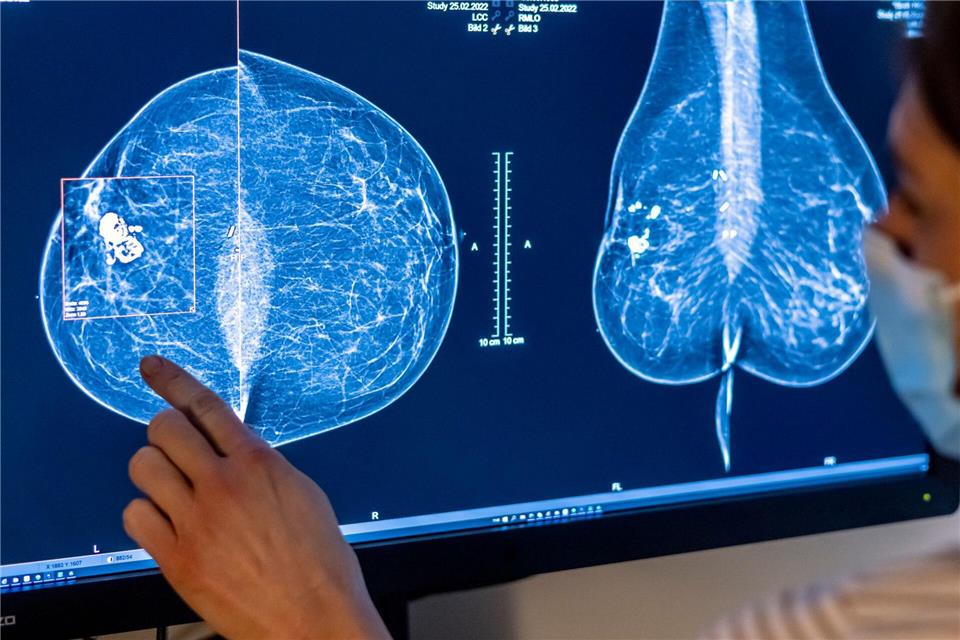

Je früher Brustkrebs erkannt wird, desto besser sind die Heilungschancen. (Archivbild)Hannibal Hanschke/dpa

„Brustkrebs ist und bleibt die häufigste Krebsneuerkrankung bei Frauen“, teilte IKK-Südwest-Chef Jörg Loth mit. Besonders betroffen seien Frauen ab 50 Jahren. Deshalb seien regelmäßige Vorsorgeangebote wie das Mammografie-Screening sehr wichtig. „Früherkennung ist der Schlüssel – je früher Brustkrebs entdeckt wird, desto besser sind die Heilungschancen“, sagte er.